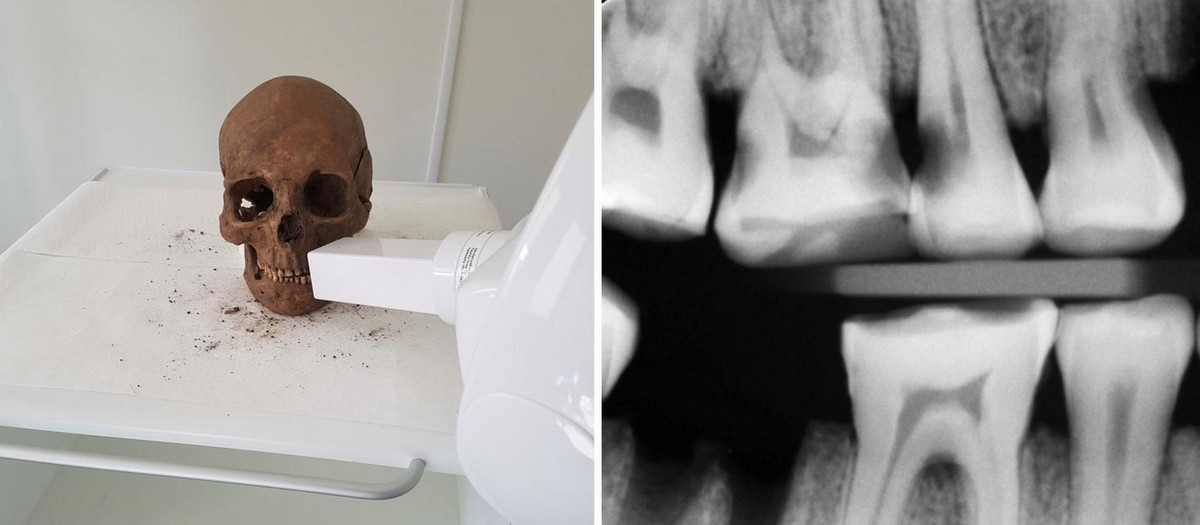

Badatelé zuby Vikingů vyšetřili s pomocí standardních zubařských nástrojů a pořídili velké množství rentgenových snímků s využitím zubního rentgenu a postupů, s nimiž se dnes setkáváme s zubních ordinacích. Výsledky výzkumu nedávno zveřejnil vědecký časopis Plos ONE.

Bertilssonová a její spolupracovníci zjistili, že 49 procent Vikingů mělo jeden či více zubních kazů. U dospělých bylo kazem postižených 13 procent zubů, často na kořenech. U dětí s mléčnými badatelé žádné kazy nenašli. Dospělí Vikingové přicházeli podle zjištěných údajů v průměru o šest procent zubů.

Vědci objevili řadu stop po odborných zásazích do chrupu, včetně používání párátek a dalších metod čištění zubů, nahrazování ztracených zubů a dokonce i léčby zanícených zubů. Narazili například na stoličky se vyplněnými otvory, zřejmě ve snaze ulevit urputné bolesti při infekci zubu. Podle Bertilssonové je fascinující, jak se tehdejší zákroky podobají ošetřením zubů dnešními zubaři.